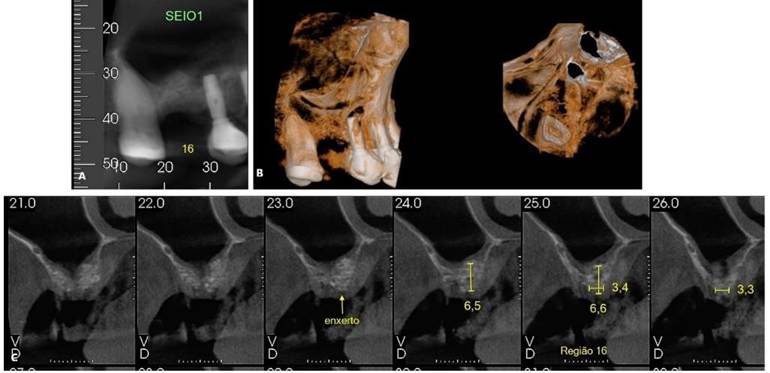

Foram solicitados exames complementares, incluindo radiografia panorâmica e tomografia computadorizada, para avaliação precisa da região anatômica, permitindo a quantificação da espessura e altura óssea (Figura 01. A-D). O plano de tratamento consistiu pela instalação de implantes ultrashort ARCSYS (FGM, Joinvile – SC, Brasil) 4,3 mm x 5,0 mm.

Figura 01. A – D) Exames de imagem complementares evidenciado aspecto inicial da região atrófica na maxila superior direita (área do elemento dental 16).